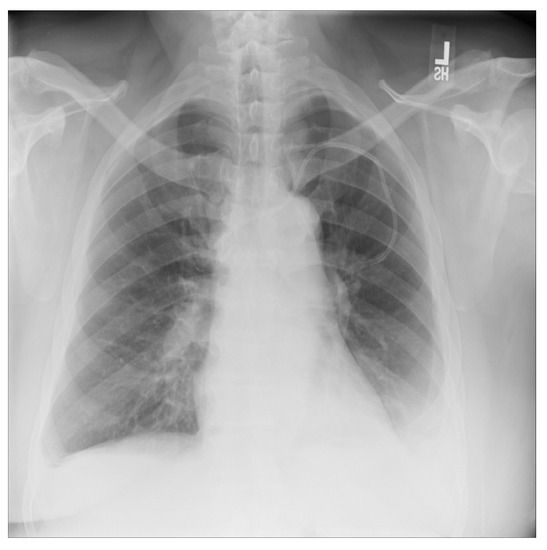

For a more intuitive understanding, we visualize a sample of each category in Figure 9, Figure 10 and Figure 11.

Figure 10. Pneumonia sample: X-ray Image dataset.

Applsci 13 00454 g010

Figure 11. Normal sample: X-ray Image dataset.